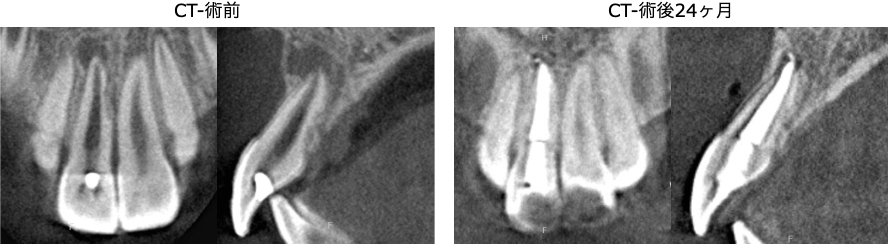

術後24ヶ月のCT画像にて、根の先の黒い影が消失し、骨が回復していることが確認できます。

腫れや痛みの症状もなく、経過良好といえます。

外傷歯の場合、根の先の吸収やクラックなど、さまざまな問題を併発していることがあります。

今回のケースでも、根管の外部吸収が認められ、予後にやや不安が残る状態でした。

患者様の年齢も考慮し、できるだけ侵襲が少ない方法で治療を行い、術後24ヶ月では良好な状態を維持できています。

今後、新たな外傷が起こると歯が完全に破折してしまう可能性もあるため、できるだけ前歯の外傷が起こらないよう気をつけていただきながら、経過を追っていきたいと考えています。